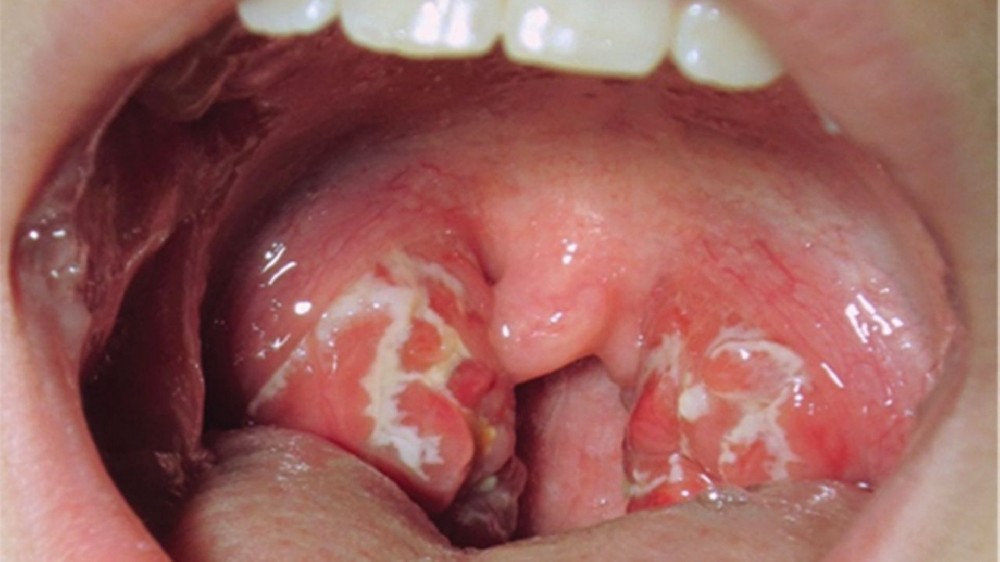

口咽癌(喉癌)的症狀

認識口咽癌(喉癌)的早期症狀可確保及時診斷,增加成功治療的機會。根據疾病的階段和腫瘤在喉嚨或口咽部結構內的位置,症狀會有很大的差異。

口咽癌(喉癌)早期症狀

疼痛或無痛的持續性喉嚨痛持續兩週以上

感覺喉嚨或頸部有腫塊,且無法自然消退

吞嚥困難(吞嚥困難),尤其是固體食物

聲音明顯改變或持續性聲音沙啞

慢性咳嗽,有時伴有微量帶血的痰液

共用神經通路導致的耳痛(轉介性耳痛)

不明原因的體重下降和食慾不振

當發現上述一種或多種症狀時,應立即進行醫療評估,以排除口咽癌(喉癌)的可能性,或在早期階段尋求有效的治療。早期發現和即時介入對於確保患者的最佳療效和長期康復至關重要。